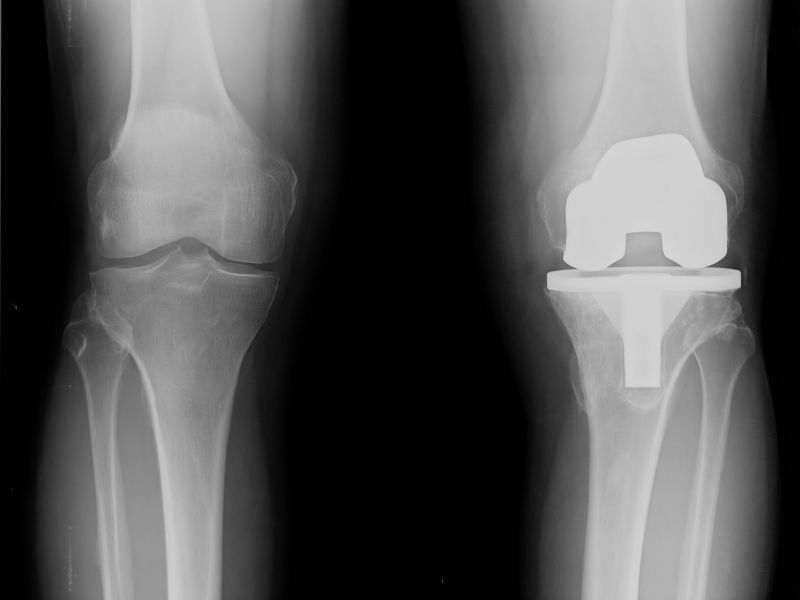

Diz ağrısının tedavisi ağrının nedenine ve şiddetine göre değişir. Dinlenme ve buz uygulaması ağrıyı azaltıp şişliğin giderilmesine yardımcı olabilir. Bunların yeterli olmadığı durumlarda hekim kontrolünde ilaç tedavisi, fizik tedavi uygulamaları, enjeksiyon tedavileri veya cerrahi müdahale gerekebilir.

Cerrahi tedavi kararı problemin ciddiyetine ve ameliyatsız tedavilere verilen yanıta bağlıdır. Menisküs yırtığı, çapraz bağ zedelenmesi veya ileri düzey kireçlenme durumlarında ameliyat seçeneği değerlendirilebilir.